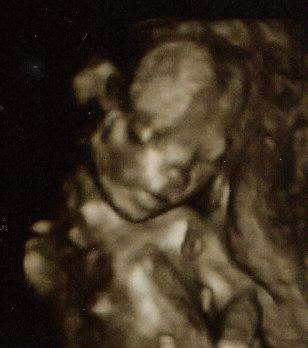

Don’t worry about the strange anomalies from the 4D ultrasound. They assure me that our little guy doesn’t really have ram’s horns or Princess Leia buns on his head. He does appear to be sucking his thumb, though. Wow.

4D?

can I suggest that it should be a 3 and not a 4?

Ah yes – here it’s 3, but in the office it’s 4, with the additional dimension of time. You get to watch the little guy moving around in real time and, in some cases (though not ours), take home a video. Wild.